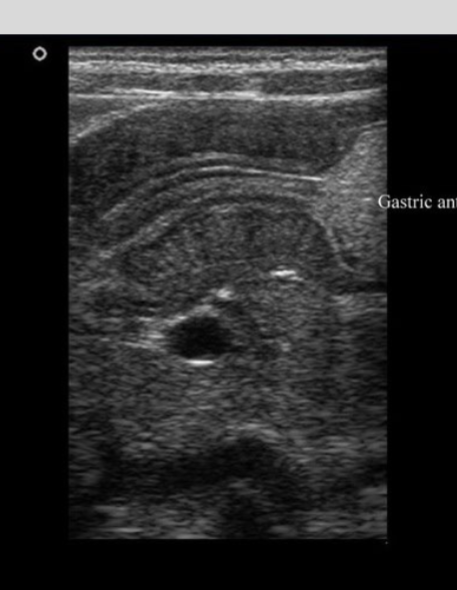

What is the primary advantage of ultrasound in medical imaging?

Ultrasound uses high-frequency sound waves and has no ionizing radiation, making it safe and cost-effective compared to other modalities.

Describe the preferred radiologic approach to detect gallstones and acute cholecystitis

Ultrasound is the first choice modality to detect gallstones and diagnose acute cholecystitis, showing echogenic stones and gallbladder wall thickening